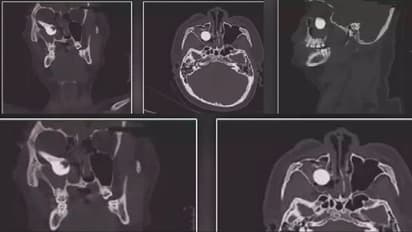

ಅಪಘಾತಕ್ಕೆ ತುತ್ತಾದ ಯುವಕನಿಗೆ ಮಾಡಲಾದ ಸ್ಕ್ಯಾನಿಂಗ್ ಕಾಫಿಯ ಚಿತ್ರಗಳನ್ನು ಅಮೆರಿಕಾದ ನೇತ್ರ ವಿಜ್ಞಾನ ಜರ್ನಲ್ನಲ್ಲಿ ( American Journal of Ophthalmology Case) ಹಂಚಿಕೊಂಡ ವೈದ್ಯರು, ಅದು ಹೇಗೆ ಕೆಲವೇ ಮಿಲಿಮೀಟರ್ಗಳ ಅಂತರದಲ್ಲಿ ಅವನ ಕಣ್ಣುಗುಡ್ಡೆಯಿಂದ ಜಸ್ಟ್ ಮಿಸ್ ಆಯ್ತು ಎಂಬುದನ್ನು ಹಂಚಿಕೊಂಡಿದ್ದಾರೆ. ಅಪಘಾತವಾದಾಗ ಬ್ರೇಕ್ ಹ್ಯಾಂಡಲ್ ಯುವಕನ ಕಣ್ಣು ಸೇರಿದ್ದರಿಂದ ಬೈಕ್ನಿಂದ ಅದನ್ನು ಕಟ್ ಮಾಡಿ ತುರ್ತು ಚಿಕಿತ್ಸೆಗಾಗಿ ಆಸ್ಪತ್ರೆಗೆ ಕರೆತರಲಾಗಿತ್ತು ಎಂದು ವೈದ್ಯರು ತಿಳಿಸಿದ್ದಾರೆ. ಆಸ್ಪತ್ರೆಗೆ ಆಗಮಿಸಿದ ವೇಳೆ 19ರ ತರುಣನ ಕಣ್ಣು ಕೆಂಪಾಗಿತ್ತು ಮತ್ತು ಊದಿಕೊಂಡಿತ್ತು, ಬ್ರೇಕ್ ಹ್ಯಾಂಡಲ್ ನಂತರ ಬಲಗಣ್ಣಿನ ಕಣ್ಣು ಗುಡ್ಡೆಯ ಸಮೀಪದಲ್ಲಿ ವಿಚಿತ್ರವಾಗಿ ಚಾಚಿಕೊಂಡಿತ್ತು, ಆದರೆ ಅದು ಕಣ್ಣುಗುಡ್ಡೆಯನ್ನು ತಲುಪಿರಲಿಲ್ಲ. ಆದರೆ ಕಣ್ಣಿನ ರೆಟಿನಾಗೆ ಹಾನಿಯಾಗಿತ್ತು.

ವಿವರವಾದ ಪರೀಕ್ಷೆ ಸ್ಕ್ಯಾನಿಂಗ್ನ ನಂತರ, ವೈದ್ಯರು ಹುಡುಗನ ಕಣ್ಣಿನ ರೆಟಿನಾವೂ ಹಾನಿಗೊಳಗಾಗಿವೆ ಅವುಗಳಿಗೆ ಮಬ್ಬು ಕವಿದಿದೆ ಎಂದು ಹೇಳಿದರು. ( ಕಣ್ಣಿನ ಹಿಂಭಾಗದಲ್ಲಿರುವ ನರ ಅಂಗಾಂಶವಾದ ಈ ರೆಟಿನಾಗಳು ಬೆಳಕಿನ ಸೂಕ್ಷ್ಮ ಪದರಗಳು ಚಿತ್ರಗಳನ್ನು ಸ್ವೀಕರಿಸುತ್ತವೆ ಮತ್ತು ಅವುಗಳನ್ನು ವಿದ್ಯುತ್ ಸಂಕೇತಗಳಾಗಿ ಕಳುಹಿಸುತ್ತವೆ).

ಈ ಹಾನಿಯ ಜೊತೆಗೆ 17 ಸೆಂ.ಮೀ ಉದ್ದದ ಈ ಬ್ರೇಕ್ ಹ್ಯಾಂಡಲ್ ಮೂಗಿನ ಸುತ್ತಲಿನ ಮೂಳೆಯ ಭಾಗವನ್ನು ಹಾನಿಗೊಳಿಸಿತ್ತು. ಅಲ್ಲದೇ ಇಸಿಜಿ ವೇಳೆ ಅವರ ಹೃದಯ ಬಡಿತವೂ ಪ್ರತಿ ನಿಮಿಷಕ್ಕೆ ಕೇವಲ 45 ರಿಂದ 48 ರಷ್ಟೆ ಹೊಡೆದುಕೊಳ್ಳುತ್ತಿವೆ ಎಂಬುದು ಪರಿಸ್ಥಿತಿಯ ವಿಷಮತೆಯನ್ನು ಸೂಚಿಸುತ್ತಿತ್ತು(ಸಾಮಾನ್ಯ ವ್ಯಕ್ತಿಯ ಹೃದಯವೂ ನಿಮಿಷಕ್ಕೆ 60 ರಿಂದ 100 ಬಾರಿ ಮಿಡಿಯುತ್ತದೆ)